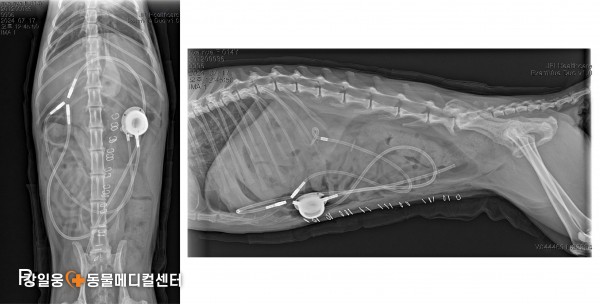

고양이 요관 폐쇄, SUB 수술로 새로운 길을 열다

SUB 수술(Subcutaneous Ureteral Bypass)

SUB 수술(Subcutaneous Ureteral Bypass) 은

요관이 막혔을 때 신장에서 방광으로 새로운 우회로

(인공 튜브)를 만들어 소변이 원활히 배출되도록 돕는 수술입니다.

쉽게 말해, 막힌 도로(요관)

대신 새로운 길을 만들어

신장에 고여 있던 소변이 다시 정상적으로

방광으로 내려가게 하는 수술입니다.

⚠️ 수술 후 주의 사항 및 예후

SUB 수술은 고양이의 요관 폐쇄에 대한 표준 치료법으로 자리 잡고 있지만,

감염, 튜브 막힘, 장치 손상, 누출 등 다양한 합병증이 생길 수 있습니다.

또한 대부분의 환자들이 이미 신장 데미지가 있는 상태에서 수술을 받기 때문에

수술 후 만성 신부전(CKD) 관리가 함께 필요합니다.

강일웅동물메디컬센터 정형·신경외과 전승하 원장은

그동안 다양한 원인으로 요관이 막힌 고양이들을 치료하며

여러 형태의 SUB 수술 사례들을 해결해 왔습니다.